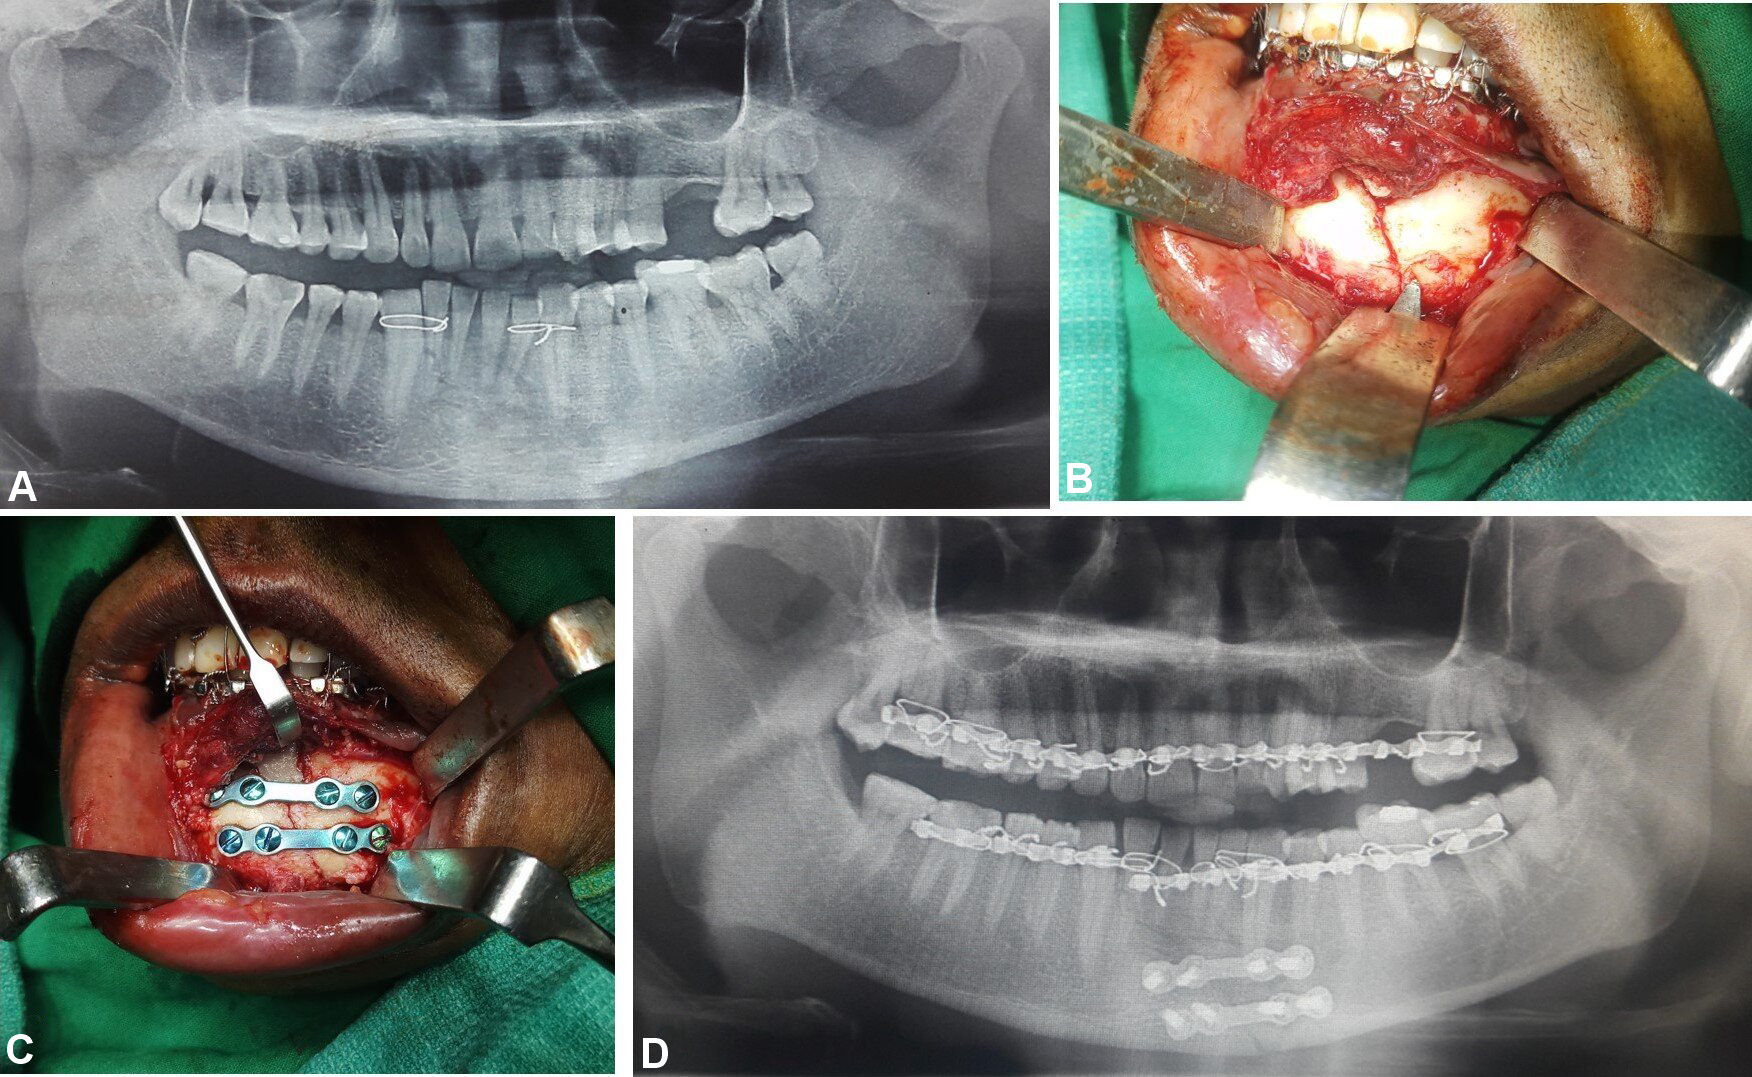

Patients with comminuted mandibular fractures, concomitant midface and dentoalveolar fractures, infected fractures, partial or complete edentulism, and systemic diseases were excluded from the study. Detailed preoperative medical and clinical examinations were conducted. The diagnosis of undisplaced or minimally displaced symphyseal or parasymphyseal fractures was based on clinical and radiographic assessments. Orthopantomograms were used to evaluate mandibular lower border displacement, with displacements of less than 5 mm included in the study (Figure 1). Advanced diagnostic techniques, including low-dose radiation and 3D assessments using computed tomography (CT), cone beam computed tomography and magnetic resonance imaging, facilitate comprehensive evaluation of head and neck disorders, including the assessment of both soft and hard tissue injuries.5, 6, 7 Therefore, CT with 3D reconstruction of the face was performed, with fractures exhibiting bucco-lingual overlap of less than 5 mm included in the study (Figure 1).

In group A, fixation was performed using 2 titanium microplates (0.8-mm, 4-hole design with a gap) and 8 microscrews (1.5 mm × 8 mm and 1.5 mm × 10 mm), which were placed subapically and at the inferior border of the mandible according to Champy’s lines of osteosynthesis (Figure 2, Figure 3, Figure 4).

In group B, fixation was conducted using 2 titanium miniplates (2.0-mm, 4-hole design with a gap) and 8 miniscrews (2 mm × 8 mm and 2 mm × 10 mm), which were positioned subapically and at the inferior border of the mandible according to Champy’s lines of osteosynthesis (Figure 5, Figure 6, Figure 7).